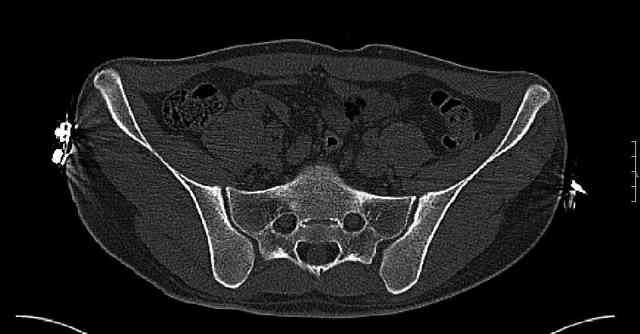

While not claiming to have the best 3D brain around, it appears to me from the limited images available, that the caudal segment is stable from the symphysis to the SI joint on the fracture side. I would love to see the rest of the transverse CT images to see where the fracture line actually exits posteriorly on both the inner and outer tables of the ilium. In my hands,

assuming that the femoral head has followed the cephalad (dome) fragment, I would use an ilioinguinal approach and take down the fracture line from anterior to posterior, distracting with a lamina spreader, if necessary, to clean out and inspect the joint. I would then reduce the cephalad fragment to the caudal fragment using jungbluth or farabeuf clamp and screws and then apply a plate and screws. If the fracture exits posteriorly would you then favor an additional posterior approach to clean out and reduce from that side?

Some more images. Does it help to guess which part of the acetabulum is displaced?

Normal appearing SI joints and a healed posterior column limb... my bet's on caudal segment displacement.